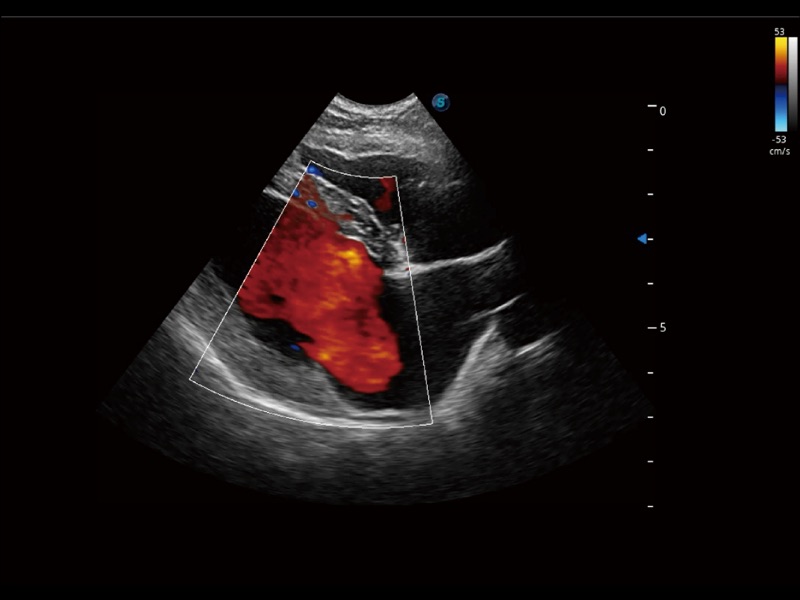

(犬)四腔心

• Micro F 显微血流成像

通过创新的 Matrix E自适应滤波器和超长时间域算法,极大提升超低速微细血流的检出能力,同时更精准地滤除软组织和噪声信号,为兽用医生提供以往无法通过常规血流获得的疾病诊断信息。